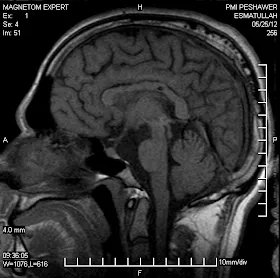

This is a young man of 26 years with c/o headache vomiting and blurred vision.

MR imaging showed an enhancing mass in the pineal region and obstructive hydrocephalus.

MR Specrtroscopy revealed alow NAA and high choline.

V.P shunt was placed and he was treated with Gamma Knife.It was a single day treatment as usual and patient was discharged next day.

At 6 months he is back to his normal life style and the Follow up MRI shows 90% resolution of the said tumor. Now at 2 years follow Pt. is fine with consistent resolution.